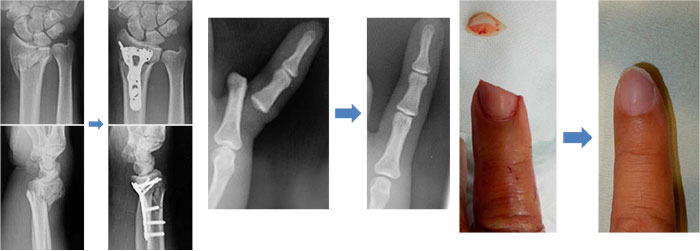

屈筋腱損傷の治療

腱を縫合・修復する手術が基本となります。手術後は、腱の再断裂や筋力の低下を防ぐため、また機能回復のため、リハビリテーションを行います。

腱の損傷の程度がごく軽い場合、お身体の状態によって手術ができない場合には、保存療法が選択されることもあります。

伸筋腱損傷の治療

伸筋腱が完全に断裂している場合には、手術を行います。手術後は、再断裂や筋力低下を防ぐため、また早期の機能回復を図るため、リハビリテーションを行います。

断裂に至っていない場合には、装具を用いた固定などに留めることがあります。その場合も、リハビリテーションは必須です。